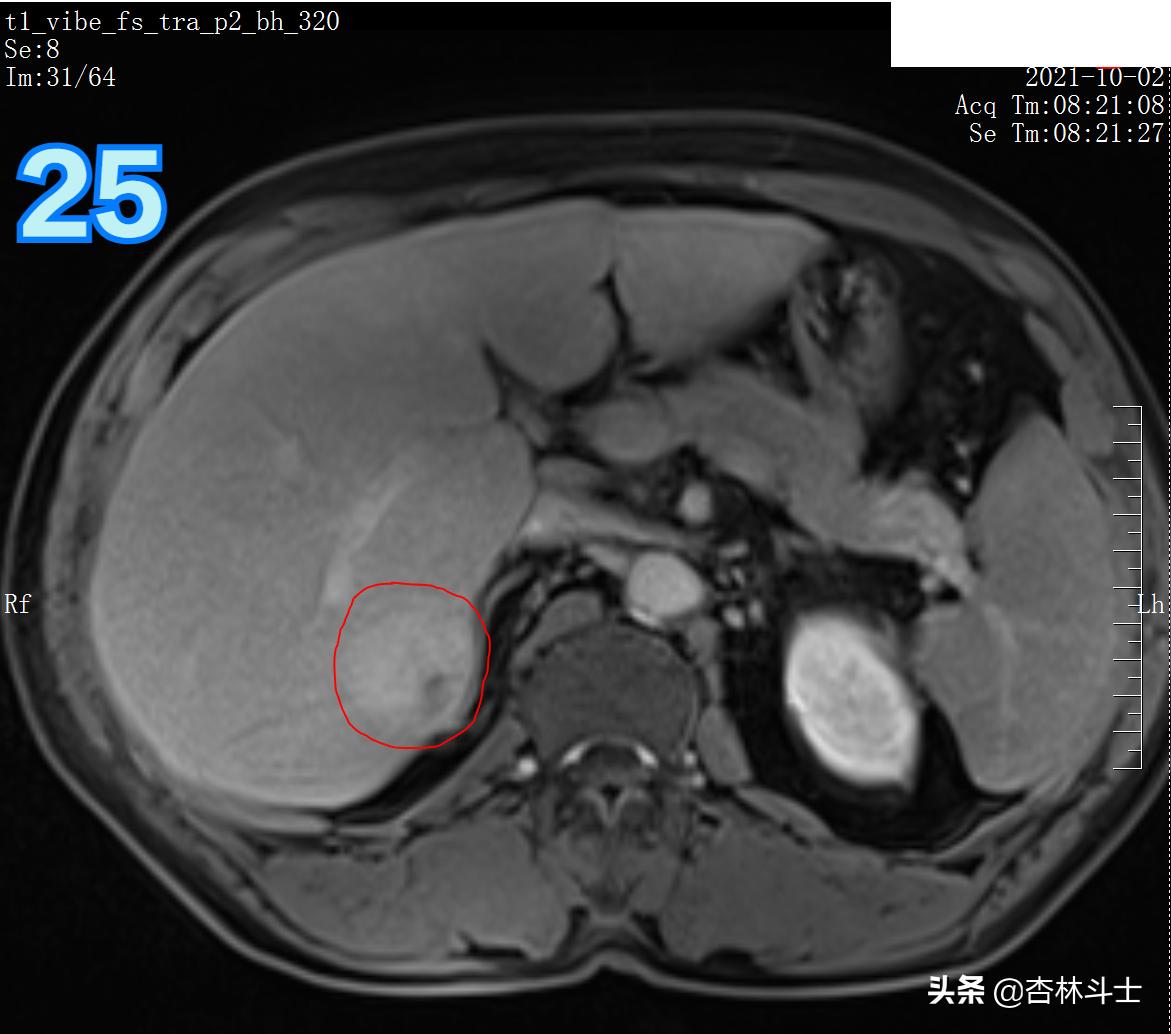

T1压脂平衡期

图25-26 T1压脂平衡期,对比剂出现廓清,病灶与周围肝实质相比,呈等或低信号。